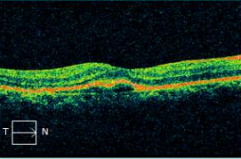

因「孔源性视网膜脱离」入院治疗的梁先生就是该课题的受益者之一。梁先生到院就诊期间,经检查,他的视网膜裂孔局限在上方且比较分散。结合他视网膜脱离的特点,黄红波在术中为其视网膜复位后,没有行常规的硅油填充手术,而是用了无菌空气填充。

对于孔源性视网膜脱离的玻璃体手术而言,硅油、惰性气体和无菌空气均可作为玻璃体腔填充物,以辅助顶压脱离的视网膜复位。与硅油填充需要进行二次住院手术取出硅油且可伴有并发性白内障、继发性青光眼等多种并发症相比,气体填充主要利用气体浮力和表面张力作用且并发症较少,同时也能为患者节约硅油使用的额外的耗材开支。